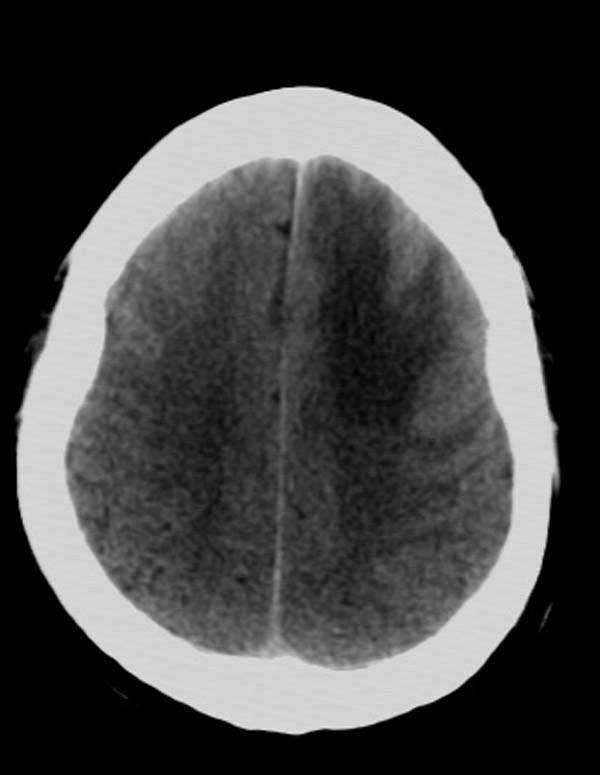

以下是引用拾荒者在2007-10-5 19:31:00的发言:[br]左额叶镰旁不规则形高密度影,中间见钙化灶及略低密度影,占位征象明显,周围有低密度水肿带环绕,首先考虑脑膜瘤。